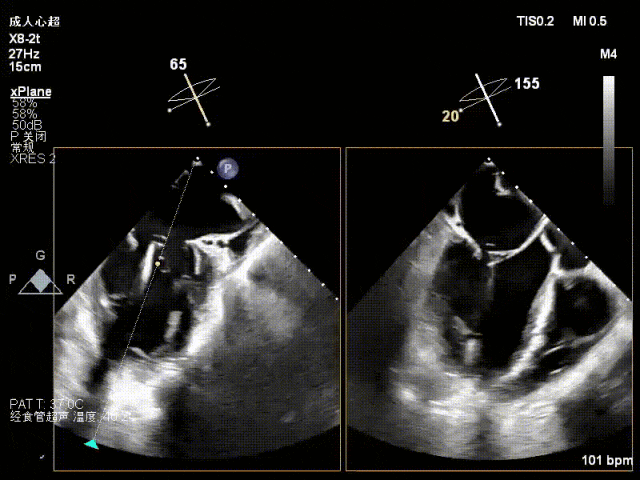

术中超声要点

术前术后对比图

术前

术后

术后,出院检查报告显示:夹子位置固定,二尖瓣轻度反流,左室稍大,LVEF值正常范围,左室壁运动分析未见明显异常(左室壁运动记分指数1分)